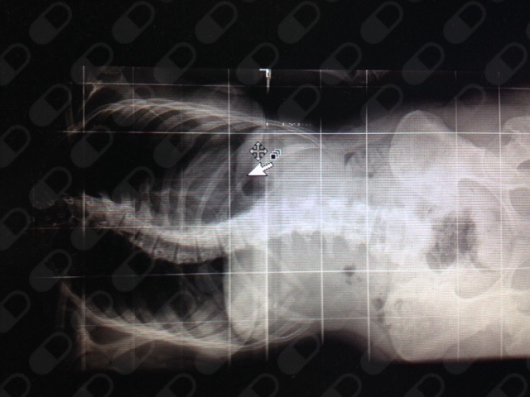

Se ha dedicado a la cirugia de columna vertebral tanto el patologia degenerativa como en deformidades escoliosis, dorso curvo, patologia tumoral de columna, hernias de disco y manejo del dolor lumbar.

Ha desarrollado una amplia experiencia en Cirugía MINI INVASIVA DE COLUMNA LUMBAR ( MISS) .

• Cirugía de Columna

• Escoliosis

• Alteración en la columna vertebral